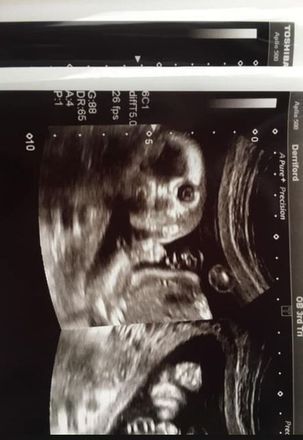

Uma mãe grávida ficou um tanto surpresa e chocada quando viu o filho encarando a câmera de uma forma um tanto sinistra

Jo Greer, 34 anos, mora em Plymouth (Reino Unido) e está grávida de 20 semanas, e foi fazer o exame para saber se está tudo bem com a criança

Mas aconteceu algo um tanto raro e até assustador: a criança olhou para a câmera

Apesar do choque da primeira reação, Jo afirma que a imagem a divertiu depois

"Foi bastante assustador, foi um choque. Mas depois, eu e meu parceiro apenas nos viramos um para o outro e caímos na gargalhada", conta ela para o tabloide inglês The Sun

"Aparentemente, não há nada de errado com isso, mas nos disseram que é bastante raro que o bebê olhe para a câmera"

Os dois estão mantendo a surpresa sobre o sexo do bebê e já sabem o que farão com a foto da criança encarando a câmera

Eles irão imprimir e dar para o filho quando ele fizer 18 anos

"Vamos manter a imagem e colocá-la no cartão de aniversário de 18 anos como uma risadinha"